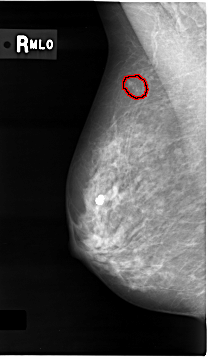

C_0012_1.RIGHT_MLO

RIGHT_MLO LINES 4664 PIXELS_PER_LINE 2696 BITS_PER_PIXEL 12 RESOLUTION 50 OVERLAY

FILE: C_0012_1.RIGHT_MLO.OVERLAY

TOTAL_ABNORMALITIES 1

ABNORMALITY 1

LESION_TYPE CALCIFICATION TYPE PLEOMORPHIC DISTRIBUTION CLUSTERED

ASSESSMENT 5

SUBTLETY 4

PATHOLOGY MALIGNANT

TOTAL_OUTLINES 1

BOUNDARY